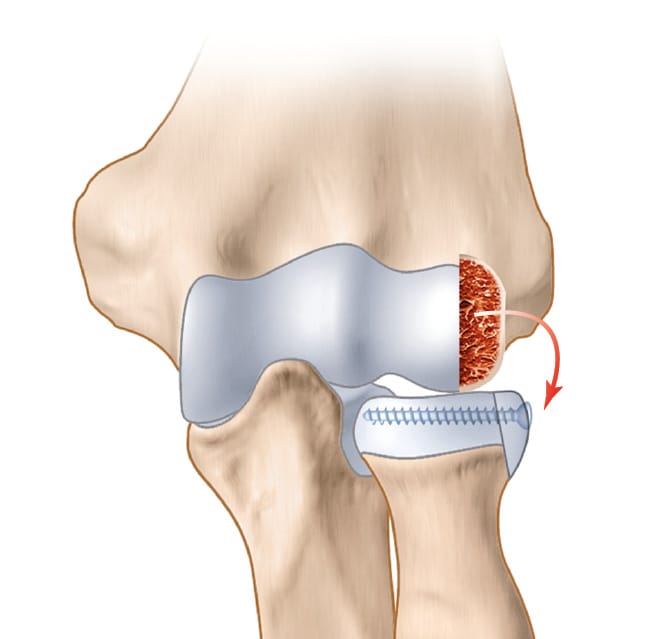

A lateral approach is used to open the radiohumeral compartment; this may be easier if there is an injury to the lateral collateral ligament, which is often part of the picture in complex joint trauma. Exposure of the radial head, the bone fragments and capitellum follows the same method whether for ORIF or replacement. Related interventions, such as coronoid process ORIF or reinsertion of the anterior capsule, are performed. A standard ORIF is carried out by reducing the fragments and temporary fixation with pins. This is followed by an assessment of bone loss: circular segment or chunk. The bone loss contour is mapped onto the lateral surface of capitellum. If the segment is circular (Figure 1), the length of the line is measured and transferred. A mini oscillating saw is using to harvest a graft with a sagittal thickness of 4–5 millimetres, depending on the extent of bone loss. The ORIF is performed using mini screws of 1.5 or 2mm diameter (Figure 2), with or without a console plate, exercising caution in the “safe zone” to avoid any proximal radio-ulnar impingement. A cancellous bone graft can also be harvested if necessary. The osteochondral graft is harvested in the sagittal plane and positioned in the axial plane, with the lateral surface of capitellum (the graft) becoming the superior surface of the radial head.

ORIF of the radial head seems to be accessible from the left side. After exposure, reconstruction proves not to be possible. A capitellum graft is harvested and fracture repair is achieved through a Medartis plate (Figure 4).